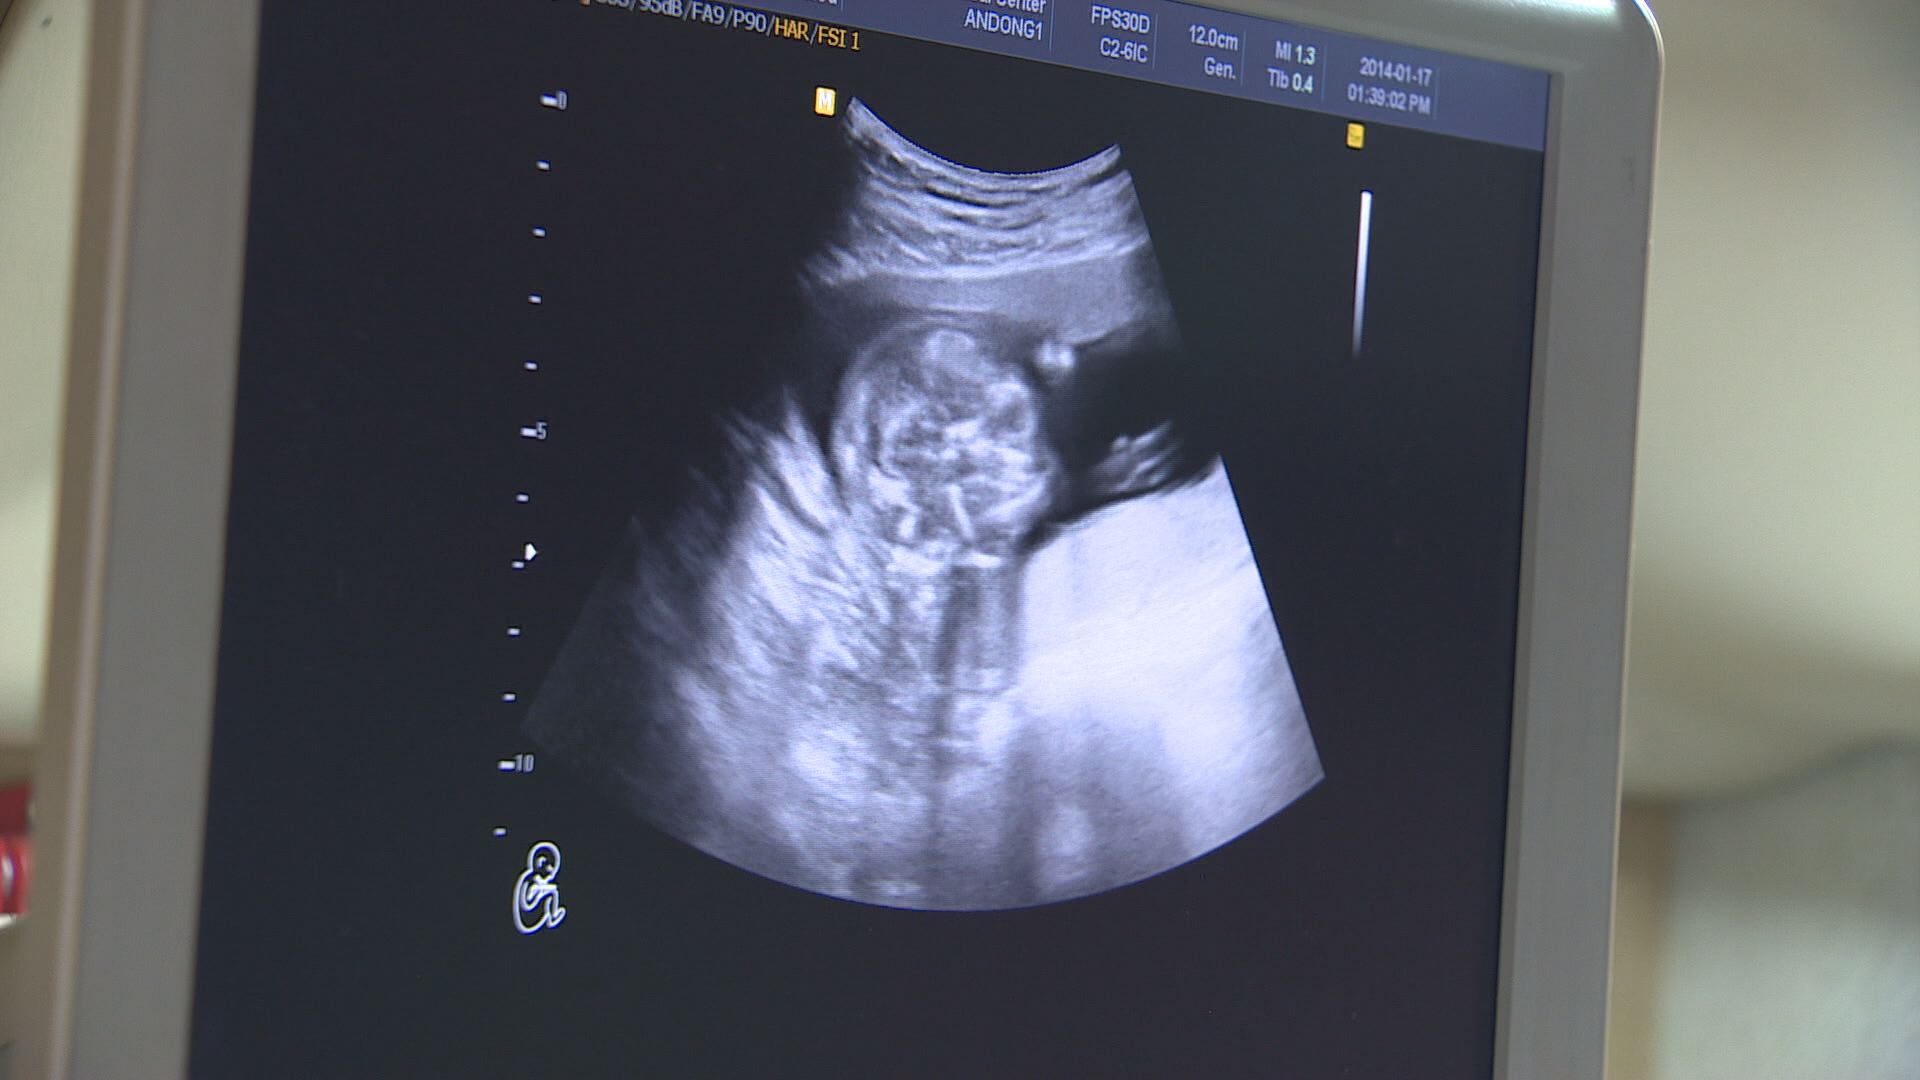

대구시는 기준 중위 소득 180% 이하 가정에만 했던 난임부부 시술비 지원을 2023년부터 모든 난임부부로 확대했습니다.

또 기준 중위 소득 150% 이하만 지원했던 산모·신생아 건강관리 비용도 2023년부터 기준을 없애고 모든 출산가정에 지원합니다.

산모와 신생아 건강 관리사가 출산 가정을 방문해서 산후 관리와 신생아 양육을 도와주는데요.

저출생 문제가 심각하기 때문인데요.

2022년 1월부터 9월까지 대구 출생아는 7,700여 명으로 전년도 같은 기간 8,200여 명과 비교해 6.1% 줄었습니다.

"기존의 소득 제한 기준을 폐지함으로써 모든 난임부부와 출산 가정이 혜택을 보게 됩니다."